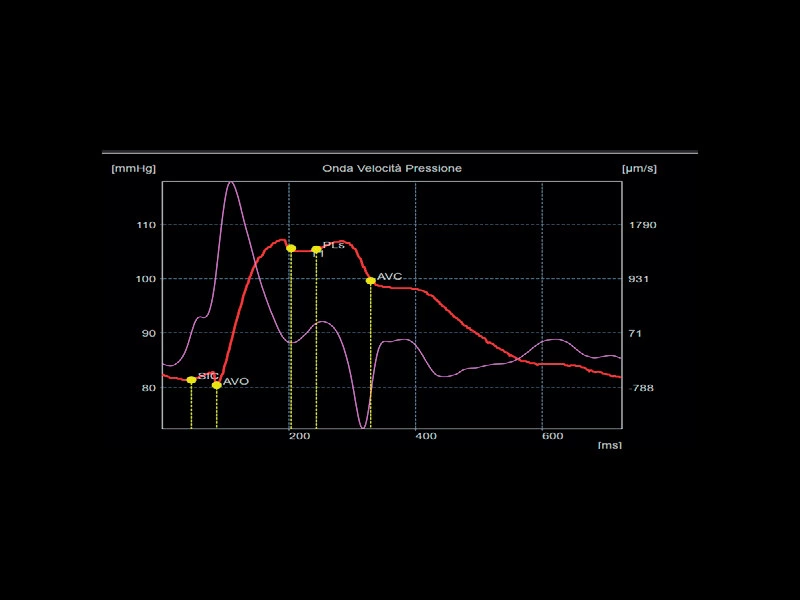

MyLab™C30 - Polm - Doppler

MyLab™C30 - Polm - Doppler